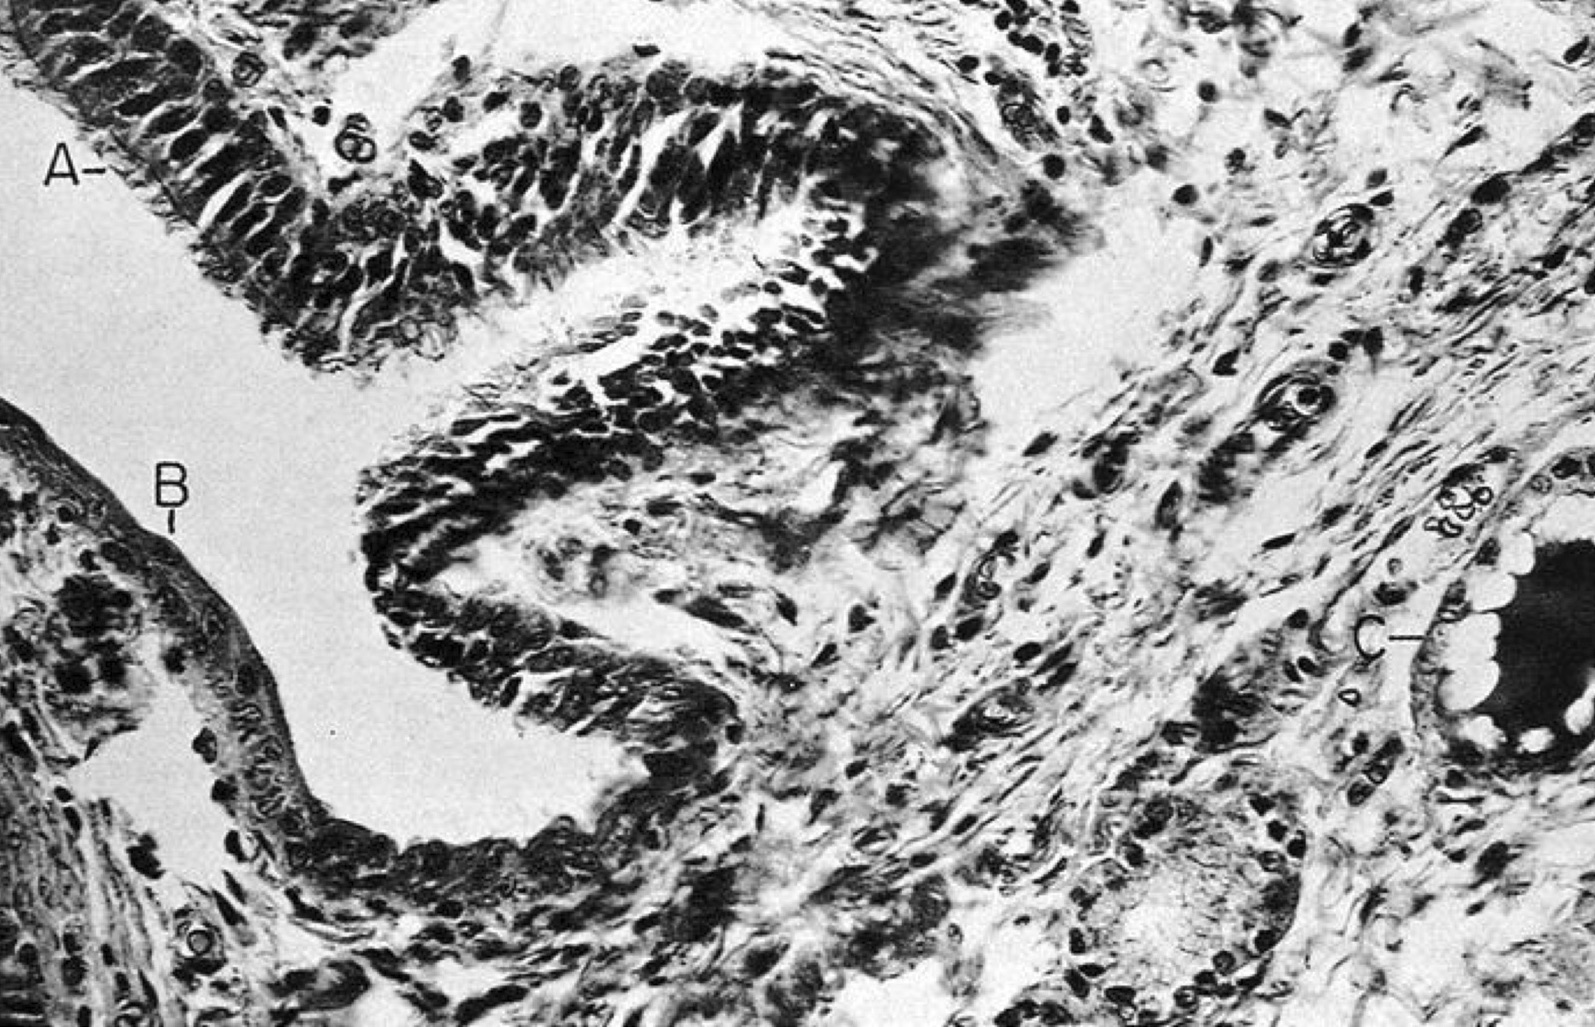

Microscopic (histologic) description

- Type of epithelial lining varies by site, and combinations of the types below can be seen in a single cyst (Head Neck Pathol 2013;7:50):

- Ciliated pseudostratified columnar (respiratory) epithelium in lower neck, perhaps due to its close proximity to upper respiratory tract

- Nonkeratinizing squamous epithelium in higher neck (near tongue and foramen cecum), also can be of metaplastic origin in inflammatory settings

- Stratified cuboidal epithelium at level of hyoid bone

- Very often the cyst is denuded of epithelium, at least focally, which reflects epithelial damage by inflammation

- Secondary inflammation is common, especially in sinus tract (J Pediatr Surg 1984;19:506):

- Intense lymphocytic infiltration, rarely arranged into lymphoid follicles

- Admixture of neutrophils (if the cyst is infected)

- Granulation tissue and fibrosis

- Thyroid follicles in the cyst / duct wall:

- Found in 30% - 60%, with higher yield on serial sections

- Seen in small irregular groups

- Thyroid epithelium may be normal or rarely hyperplastic or neoplastic

- Thyroid tissue often hidden by inflammation (Laryngoscope 2001;111:1002)

- Absence of thyroid tissue does not exclude the diagnosis of TGD cyst

- Mucous salivary-type glands can be found in the cyst wall, frequently in lingual and suprahyoid locations (Ann Otol Rhinol Laryngol 1996;105:996)

Microscopic (histologic) images

Contributed by Andrey Bychkov, M.D., Ph.D., Mark R. Wick, M.D. and AFIP

Images hosted on other servers: